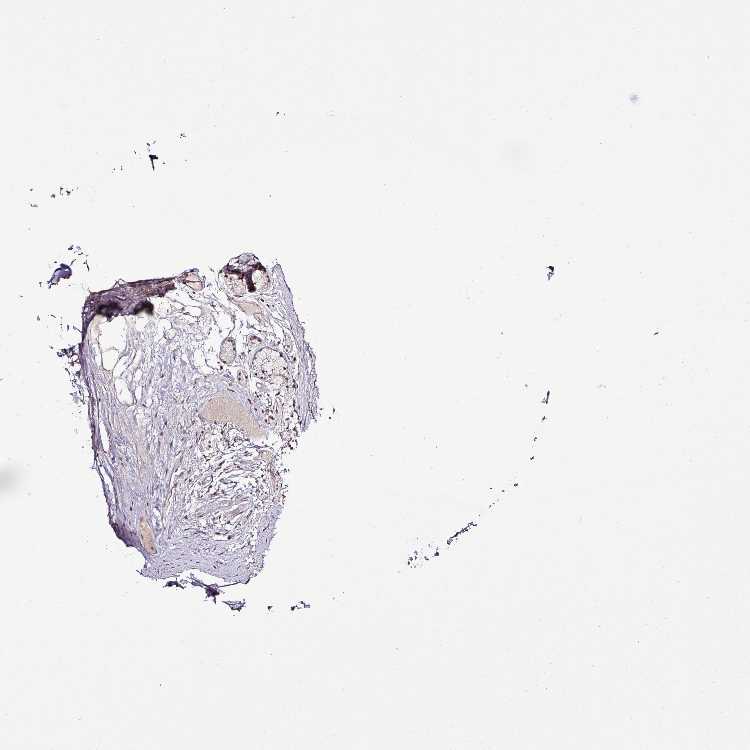

SOFT TISSUE 1 - Antibody stainingi

Antibody staining in the annotated cell types in the current human tissue is reported as not detected, low, medium, or high, based on conventional immunohistochemistry profiling in selected tissues. This score is based on the combination of the staining intensity and fraction of stained cells.

Each image is clickable and will lead to virtual microscopy that enables deeper exploration of all samples and also displays staining intensity scores, fraction scores and subcellular localization as well as patient and tissue information for each sample.

Antibody HPA053003

Chondrocytes Medium

SOFT TISSUE 2 - Antibody stainingi

Antibody HPA050760Antibody HPA053003

Fibroblasts Not detectedMedium

Peripheral nerve Not detectedMedium